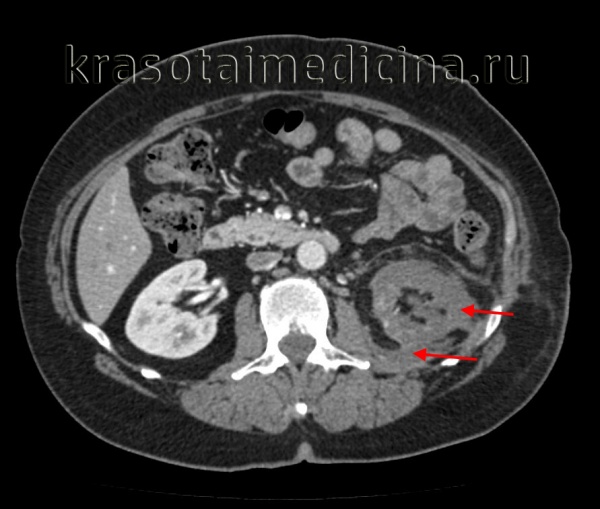

КТ ОБП/ЗП. Гнойное расплавление левой почки с формированием «мешка», заполненного гноем, с воспалительными изменениями прилежащей клетчатки.

- Рентгенодиагностика. При обзорной урографии на рентгенограмме видна тень увеличенной почки с четкими контурами. Часто обнаруживаются камни в почечной лоханке или мочеточнике, создающие механическую преграду для оттока гноя. Дополнительно используется ангиография почечных сосудов, оценивающая уровень кровоснабжения органа. КТ почек также определяет очаг, но позволяет отличить полость, заполненную гноем, от опухоли или кисты.

- УЗИ почек. Помогает локализовать воспалительный очаг, определить его форму, оценить качество уродинамики в лоханках и мочеточниках.